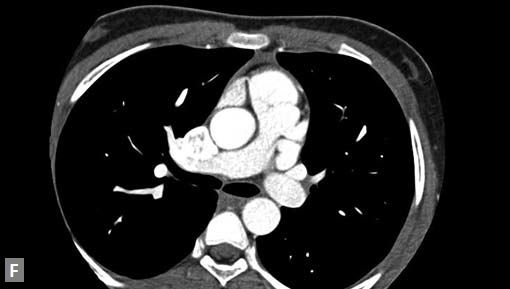

Computed tomography is not preferred mode of investigation in ostium primum and secundum defects and in fact smaller defects are often missed. Secundum type ASD is the most common congenital heart defect to present in adults. Equalization of contrast density in left and right cardiac chambers during the study is an indication of possible shunt lesion.

Primum type is seen as a defect immediately posterior to atrioventricular valves. Primum variety is associated with Down’s syndrome and other congenital anomalies. This type of ASD is a mild form of endocardial cushion defect. Secundum type is the most common variety. Usually defect is large. Associated RA enlargement, dilation of MPA (Fig. 23G) may be noted. Patent foramen ovale (PFO) and fossa ovalis mimic small secundum ASD. PFO is usually a left to right shunt with a tunnel-like appearance. Events that increase RA pressure such as coughing, Valsalva maneuver, tricuspid regurgitation (TR) can cause right to left shunt in PFO. PFO jet is directed to floor of right atrium and roof of left atrium.